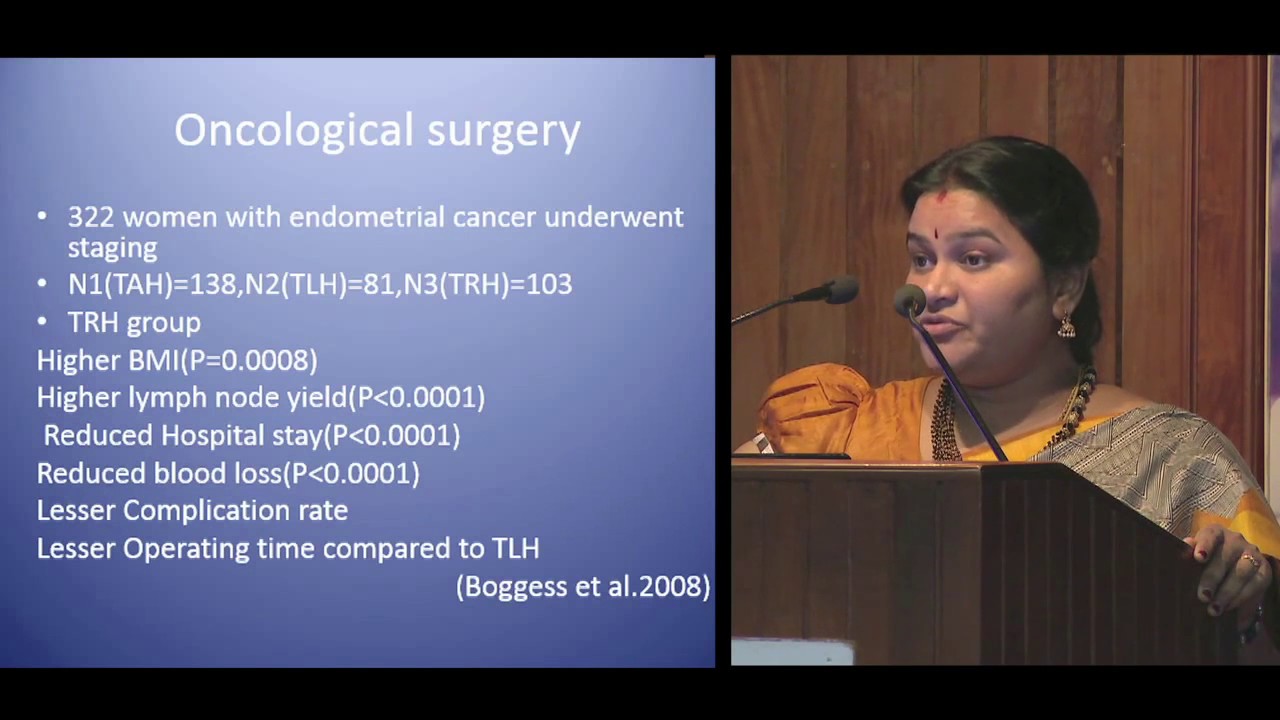

Sentinel Node Mapping in Endometrial Cancer

Gynecology, Oncology ';